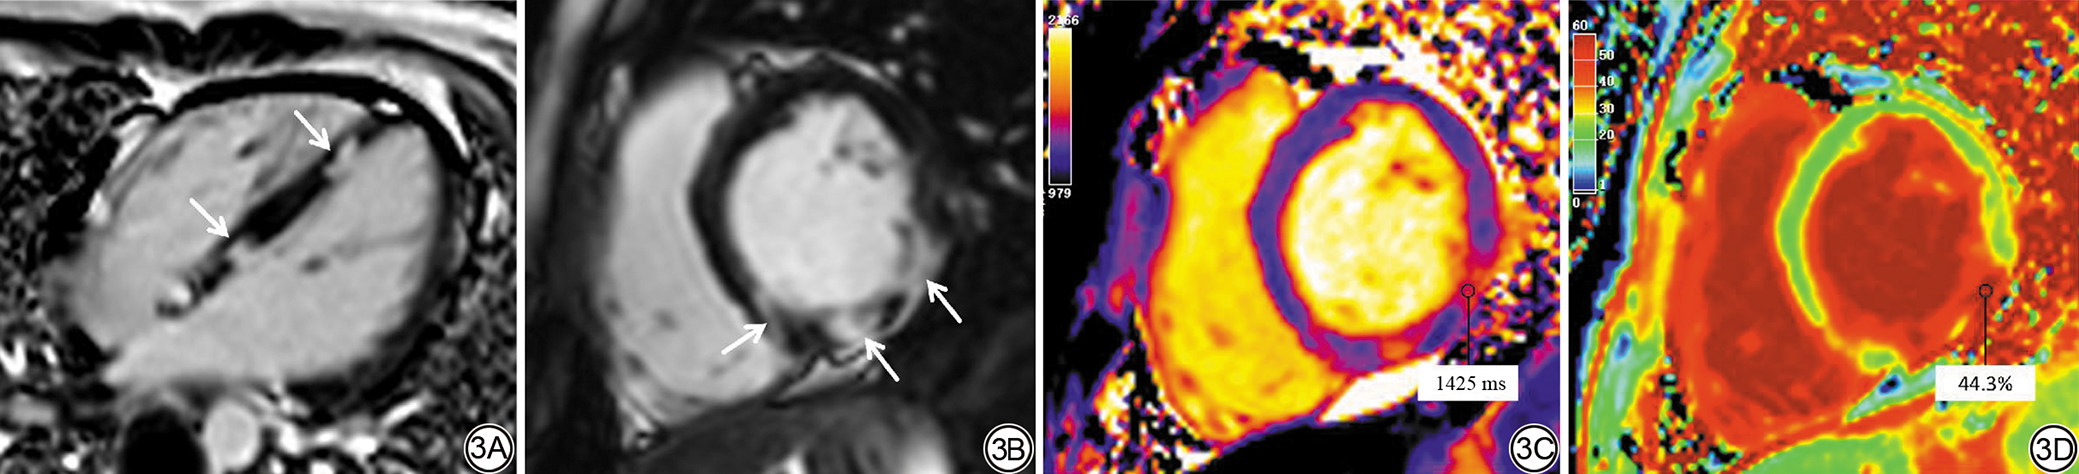

在APS患者中,进一步根据SAPS、PAPS进行亚组分析。SAPS组的RVEDVI、RVSVI、RVCI均高于PAPS组(P<0.05),而RVEF未见进一步降低(P>0.05)。左心室形态及功能学参数两组间无显著性差异。组织学方面,SAPS组的native T1值[1 294.00(1 264.75,1 327.00) ms vs. 1 245.00(1 225.50,1 297.00) ms, P=0.045] 和ECV(32.55%±4.45% vs. 27.94%±1.86%,P=0.020)高于PAPS组(表3)。按患者水平比较LGE分布类型(如心内膜下、插入部等),两组差异无统计学意义。根据AHA16节段绘制的LGE阳性率牛眼图用于展示节段分布特征,SAPS组在下壁节段呈相对集中的分布模式,PAPS组主要累及室间隔、下壁及下侧壁(图2)。在分布模式方面,SAPS心内膜下占比更高,但未达统计学差异[29.2%(7/24) vs. 16.7%(1/6),P=0.290]。图3为一例SAPS患者的LGE、T1和ECV图。

图3  SAPS患者LGE四腔心及短轴位图、T1 mapping、ECV图。患者女,18岁。3A~3B:左心室下间隔、下壁、下侧壁多发小片状强化,部分呈非冠脉分布区域高信号;3C:同上述位置native T1值升高,最高位于下侧壁,约为1425 ms;3D:ECV最高位于下侧壁,约为44.3%。SAPS:继发性抗磷脂综合征;LGE:延迟强化;ECV:细胞外容积。

Fig. 3  Representative CMR from a SAPS patient (female, 18 years old). 3A to 3B: LGE shows multiple small patchy enhancements in the left ventricular inferoseptal, inferior, and inferolateral walls, several foci are in a non-coronary distribution (arrows). 3C: Native T1 mapping demonstrates corresponding regional elevation, with a peak value of 1425 ms in the inferolateral wall. 3D: ECV mapping shows a maximum of 44.3% in the inferolateral wall. CMR: cardiac magnetic resonance; SAPS: secondary antiphospholipid syndrome; LGE: late gadolinium enhancement; ECV: extracellular volume.